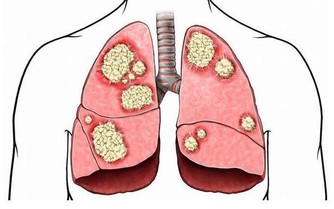

8. 你已經被診斷患有炎性疾病

狼瘡和類風濕性關節炎有兩個可怕的共同點:更可能影響女性,都會增加心髒病的風險。這一切都歸結於炎症,炎症損害血管,導致斑塊積聚。